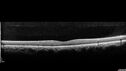

Advanced age-related macular degenerationvu 251 fois87 year old female. Severe macular bleed 15 years ago OD. Now with disciform scar. Left eye has progressing geographic atrophy.

VA OD: HM, OS: 5/200. IOP normal OU17 Mars 2024